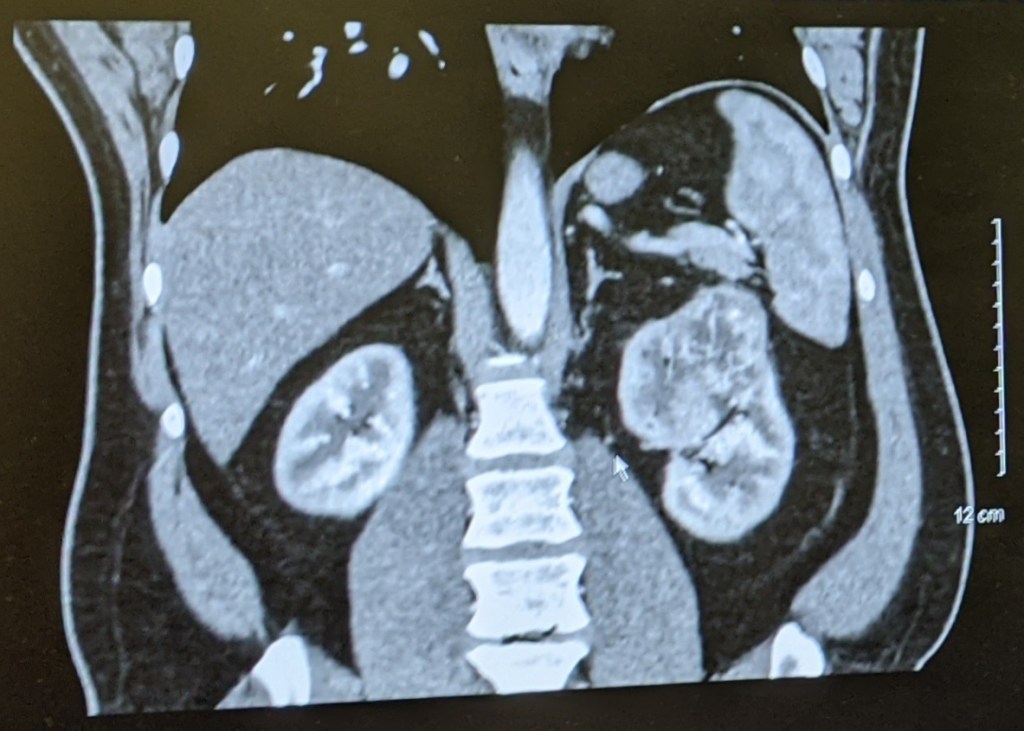

One small thing, before I go further. When Tom explained to me what was on the scan, he said it was a “dark spot.” This did not translate in my brain the way I think he thought it did. Hence my hope that it was just a weird artifact. However, this is actually what showed up. Guess which kidney is the one in question…

He has a tumor. A giant tumor. The urologist said that cancer can’t be officially diagnosed until they can actually take a look at the tumor and kidney. That said, according to the urologist so far this appears to be consistent with kidney cancer. Because the tumor is so large they are going to use the surgical robot and remove his entire kidney on May 13th.